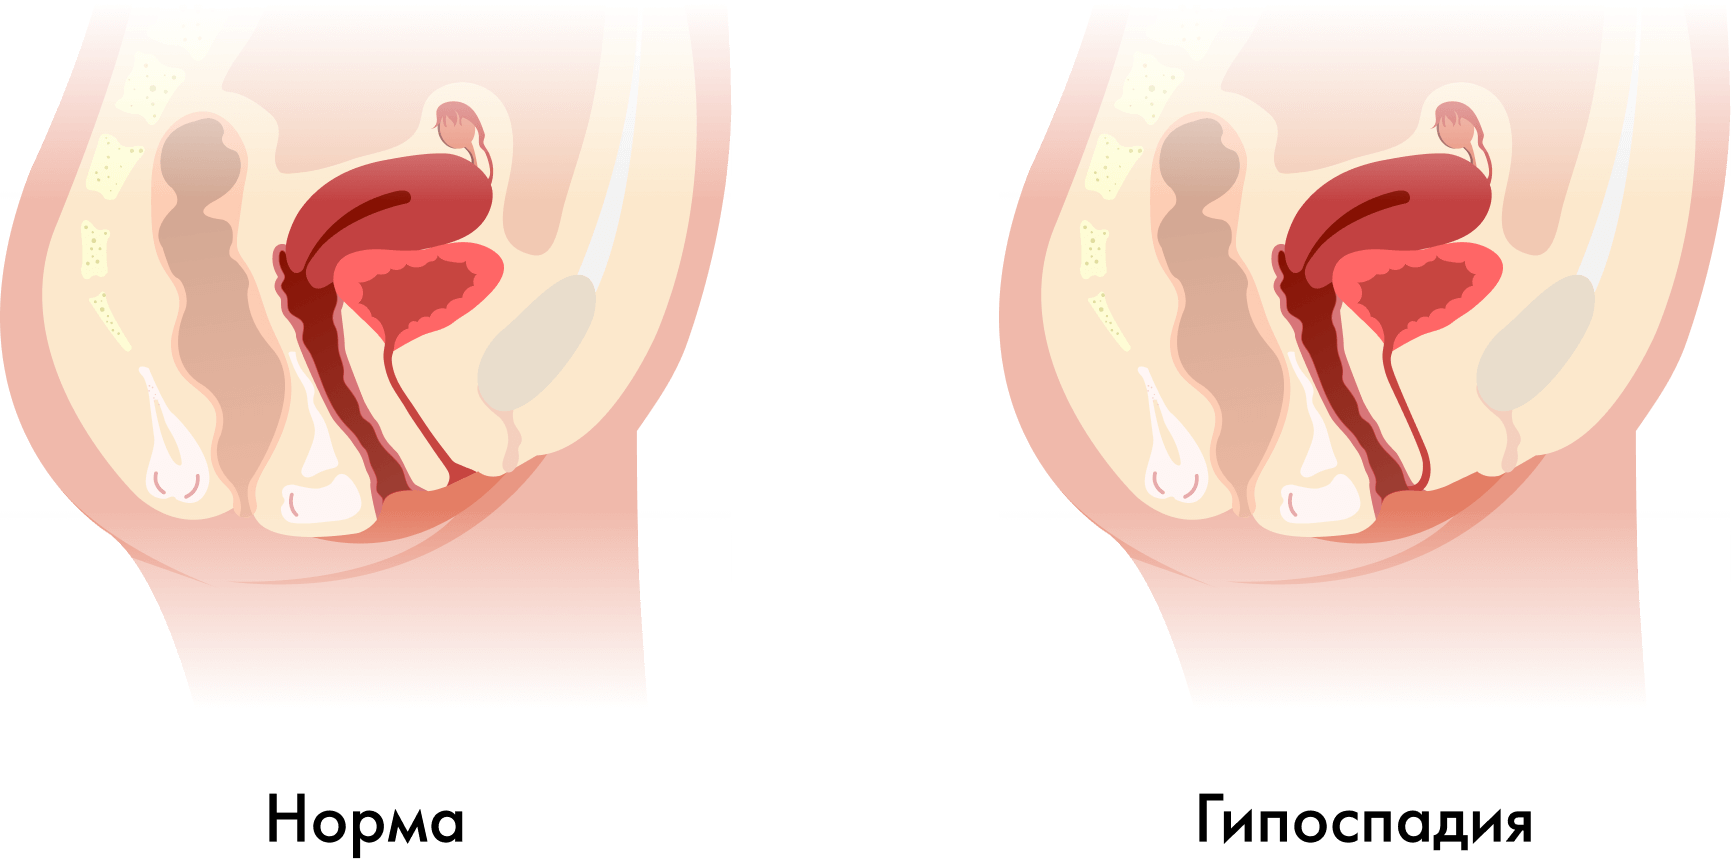

- смещение (эктопия) наружного отверстия уретры к входу во влагалище, а иногда даже на его переднюю стенку. Может сопровождаться недоразвитием и укорочением уретры;

Гипоспадия у женщин